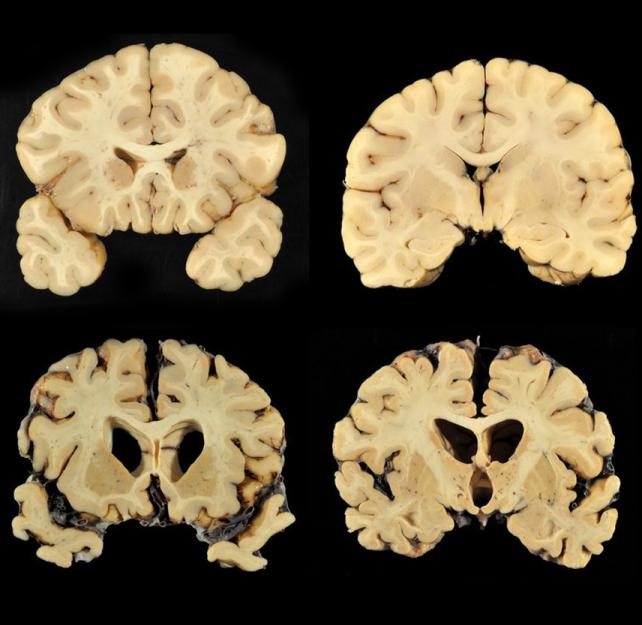

What is Chronic Traumatic Encephalopathy or CTE?